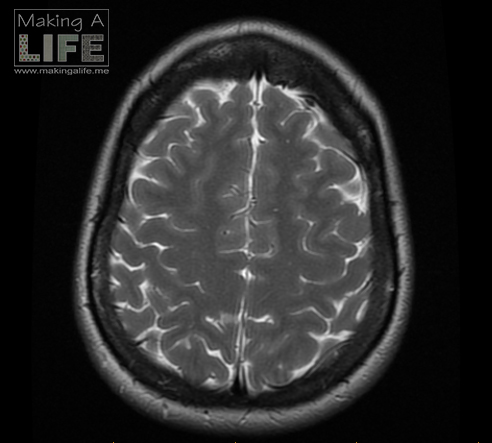

Going into surgery on August 7th, 2015 was the scariest day of my life and a close second was March 18th, 2015 standing in the emergency department in my pj’s being diagnosed with a brain tumour. The months that followed the diagnosis were challenging. My oldest son was in kindergarten my youngest in diapers. I was a mom to a 2 year old and 5 year old, first year graduate student and unsure of what the future might hold. Life was scary.

On August 7th 2015 I went into the hospital to have a meningioma tumour removed from my brain. The experience was no picnic, but I survived and a year later I am thriving. I blogged all about my brainy experiences pre and post surgery, and if you are interested in the gory details they are all there in the BRAIN TUMOUR tab at the top of every page.